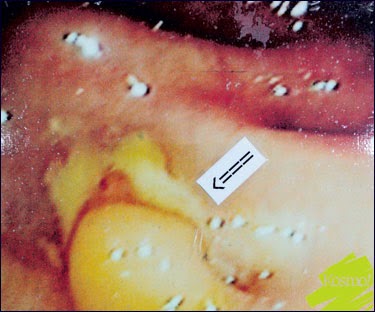

“Sembelit yang merbahaya terjadi disebabkan oleh kanser usus dan saluran najis yang tersumbat.

“Justeru, sekiranya anda mengalami sakit perut, sembelit dan najis berdarah serta kehadiran lendir yang berlarutan, jangan anggap ia adalah buasir. Seelok-eloknya, jumpa doktor dan lakukan pemeriksaan kolonoskopi.

“Ada beberapa kes yang pernah saya kendalikan menganggap sembelit dan najis berdarah hanya sebagai buasir, hakikatnya ia adalah kanser usus yang sudah serius,” ujarnya ketika ditemui Jurnal baru-baru ini.

SIMPTOM kanser usus sering dianggap gejala buasir kerana wujud persamaan iaitu sukar buang air besar.